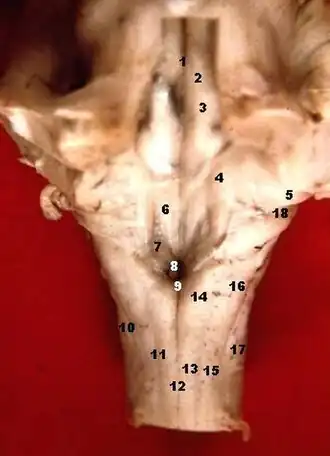

La fosa romboidal, suelo del cuarto ventrículo o fosa romboidea ([TA]: fossa rhomboidea) es la pared anterior y el suelo del cuarto ventrículo cerebral, y es la parte posterior del puente de Varolio y la médula oblongada.

La fosa consta de tres partes:[1]

- La parte superior es de forma triangular y está limitada lateralmente por el pedúnculo cerebeloso superior; su ápice, dirigido hacia arriba es continuo con el acueducto cerebral, su base está representada por una línea imaginaria a nivel del límite superior de la fóvea superior.

- La parte intermedia se extiende desde este nivel a las porciones horizontales de las tenías del ventrículo. Es estrecha en la zona superior, donde está limitada lateralmente por el pedúnculo medio, pero se ensancha hacia abajo y se prolonga en los recesos laterales del ventrículo.

- La parte inferior es triangular y su ápice dirigido hacia abajo, llamado el calamus scriptorius, es continuo con el canal central de la parte cerrada de la medula oblongada.

El sulcus limitans o cisura limitante forma el límite lateral de la eminencia medial.

Tallo cerebral humano, vista posterior.